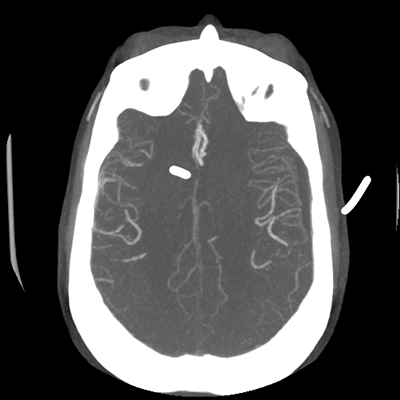

The patient goes down to CT. The following images are obtained. The subdural fluid collection is stable, as is the ventricular caliber.

Starting with the non-contrast head CT, we can appreciate that there's actually not much residual subarachnoid blood at all; it's essentially all resorbed already (and cleared through the EVD). The ventricular caliber is stable. With the CTA head (for convenience's sake, the MIPs were shown), it's subtle, but we can see that the PCAs on each side are not as smooth and regular. The right MCA, starting at the bifurcation, also becomes narrower. This is [radiographic] vasospasm. Now, looking at the CT perfusion-- specifically, the Tmax (MTT) map that were selected-- there's clearly some abnormality within the bilateral cerebellar hemispheres and occipital lobes. Not a lot, but it's there. Delving further into this map, we can appreciate that the areas of abnormality are mainly green, signifying that these areas have Tmax > 6 seconds. This is the threshold that is specific, not sensitive, for vasospasm.

Putting this all together, we have thus identified radiographic vasospasm with the vessel imaging, with perfusion abnormalities that are concordant with it. Does the area of vasospasm and hypoperfusion correlate with the patient's clinical exam?

Yes! It does. The patient had a decline in level of consciousness with diffuse loss of motor function. This does correlate to the basilar territory. (Alternatively, bilateral MCA vasospasm could also be responsible, reminding us that a decline in consciousness could technically be focal/multifocal.) Thus, we can say that this patient does have clinical vasospasm. Whether this will develop into irreversible DCI remains to be seen; at least, the non-contrast head CT and the other portions of the CT perfusion (not shown) currently don't [yet] suggest infarction.